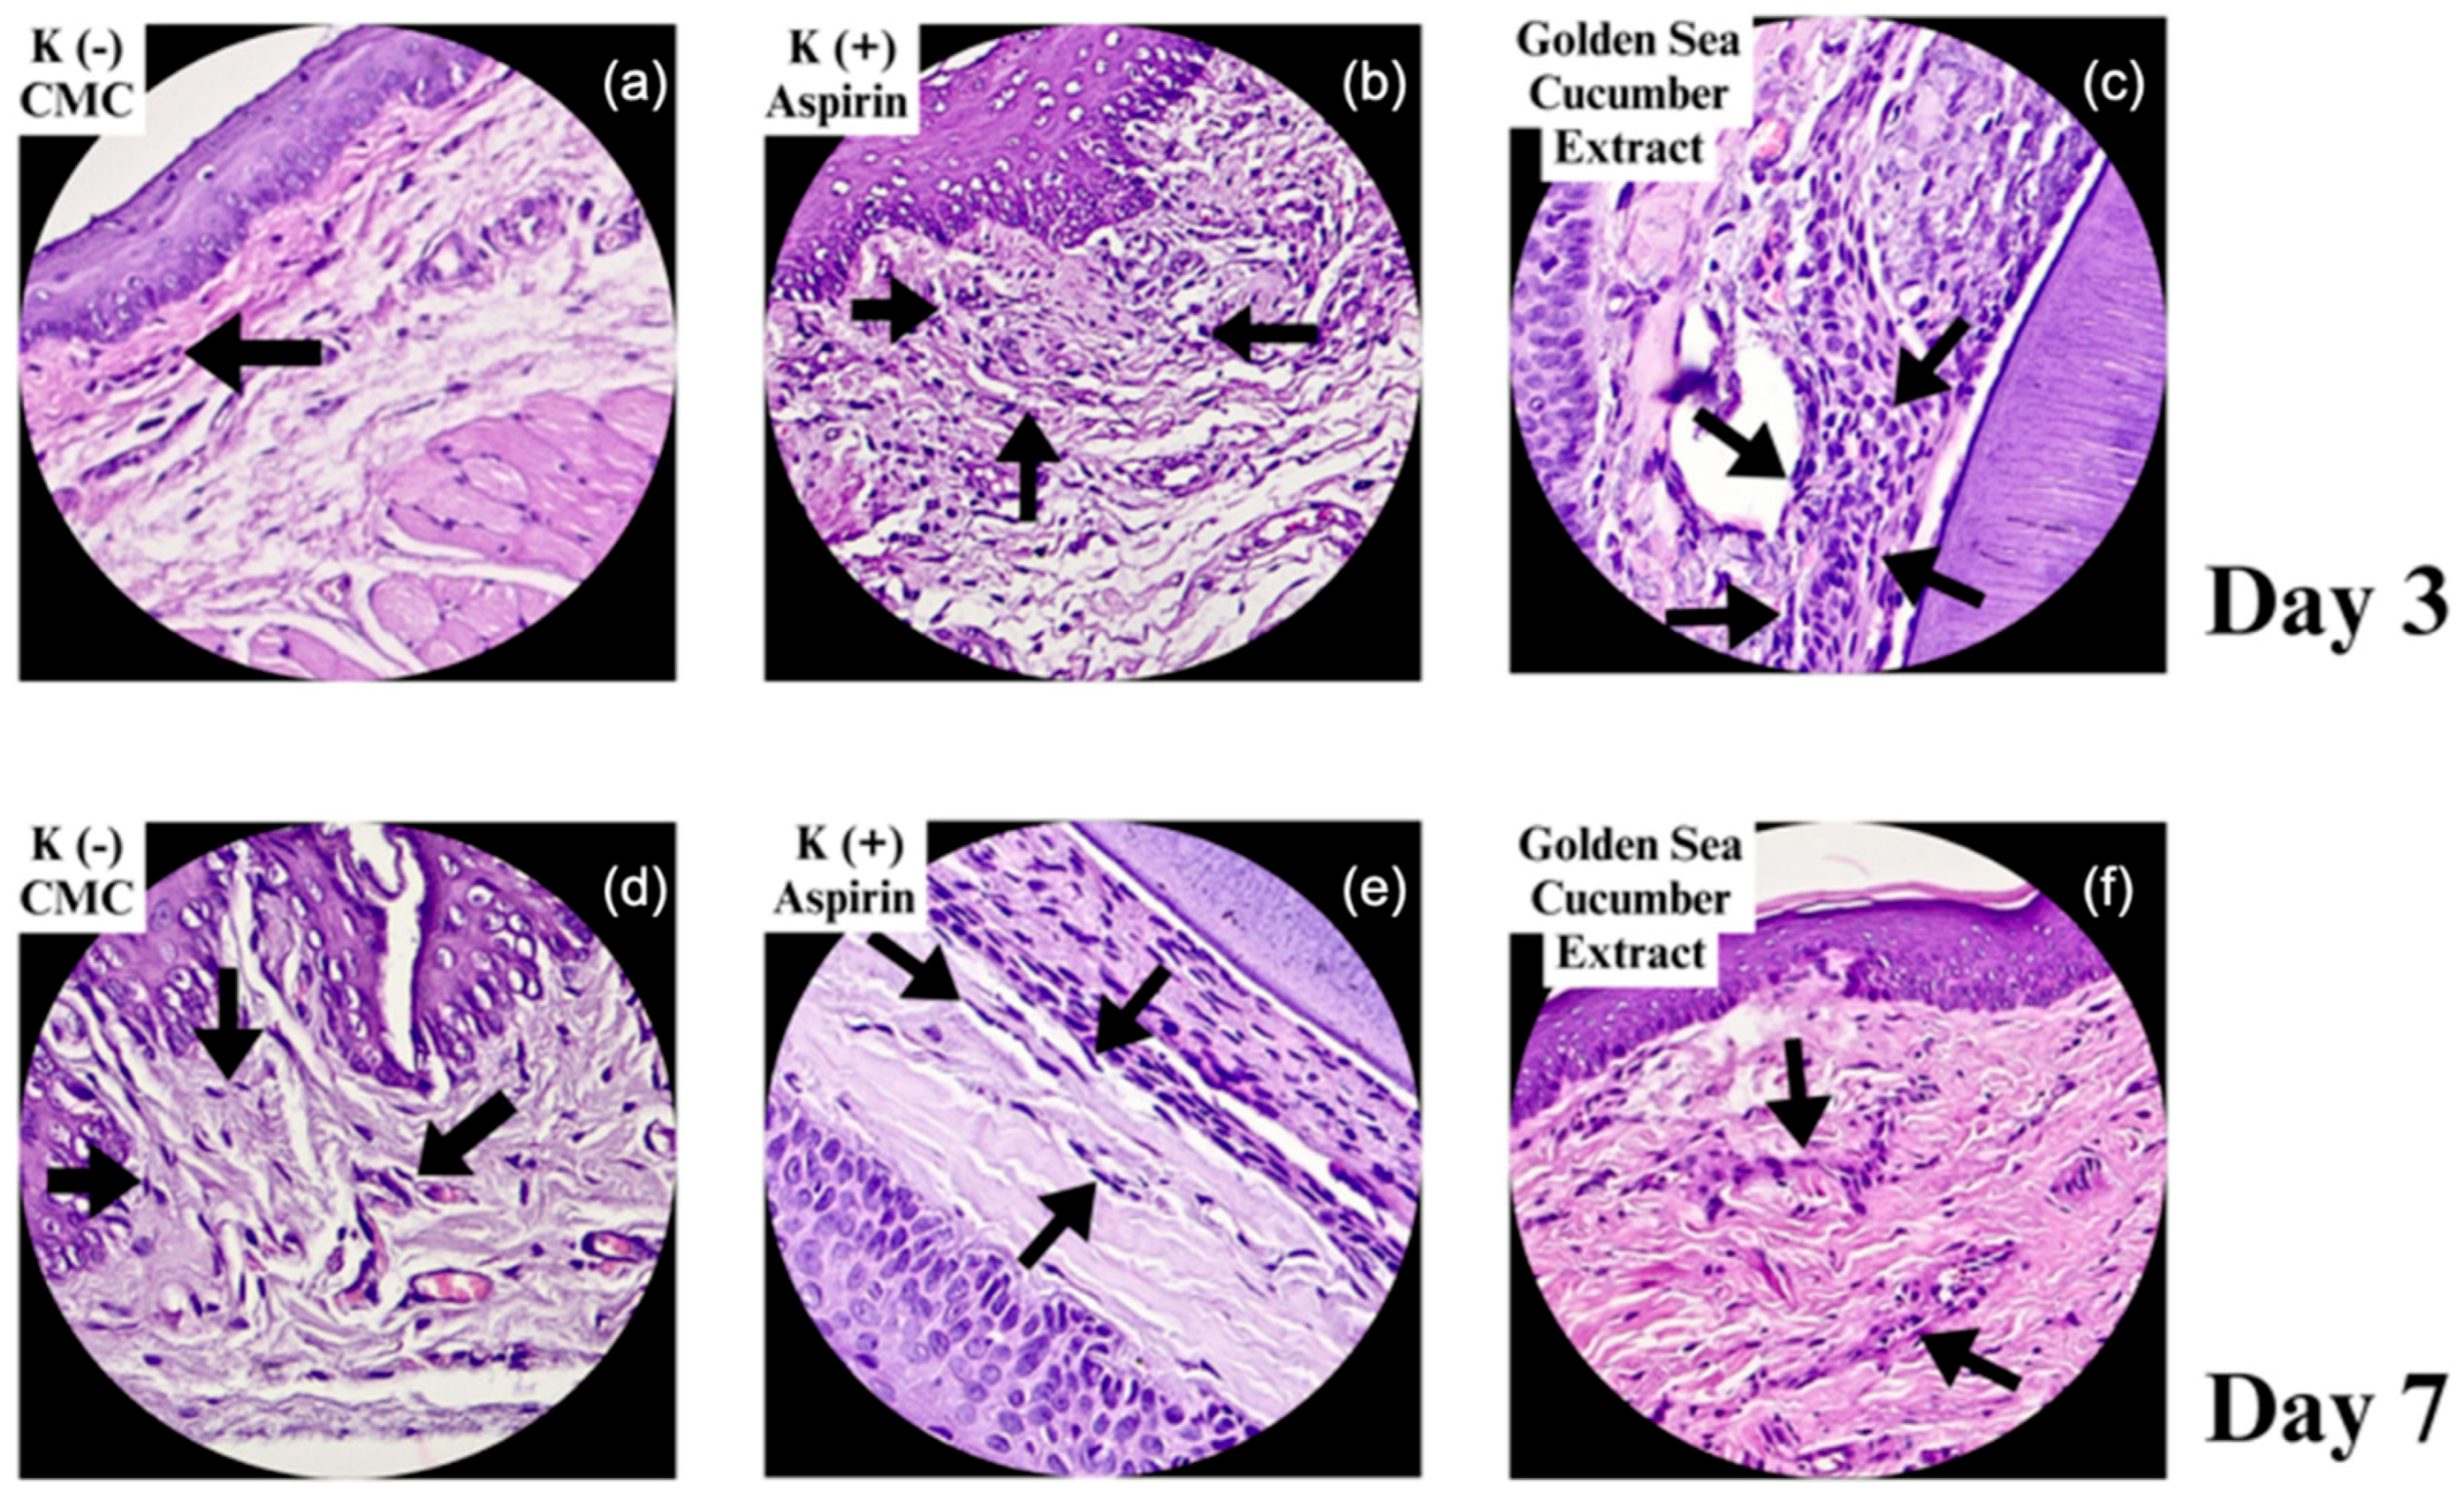

2.2. Histological Features of Fibroblast Proliferation in Gingival Wound Healing

| Group | n | Day 3 | Day 7 | ||

|---|---|---|---|---|---|

| Fibroblasts (Mean ± SD) |

Collagenization | Fibroblasts (Mean ± SD) |

Collagenization | ||

| Na-CMC | 2 | 119 ± 5.38 | 112.00 μm | 166 ± 13.8 | 175.75 μm |

| Aspirin | 2 | 177 ± 14.62 | 238.50 μm | 350 ± 24.54 | 452.75 μm |

| Stichopus hermanii | 2 | 213 ± 13.2 | 177.25 μm | 251 ± 21.7 | 717.25 μm |

| P value | 0.001* | 0.002* | 0.001* | 0.000* | |

| *One-way ANOVA test (p<0.05) | |||||